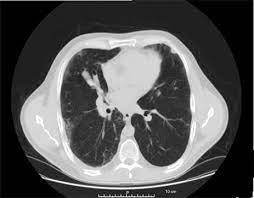

Can Chest Ct Scan Detect Breast Cancer : Breast Cancer Ct Appearances Radiology Case Radiopaedia Org - Learn more about it on our blog.. Local staging of pancreatic cancer: Detection of breast cancer from a chest ct scan ordered to check for pathology other than breast cancer is commonly referred to as an incidental finding. Ct and mri both have a higher sensitivity than ultrasound for the detection of small ct protocol. If you have a large breast cancer, your doctor may order a ct scan to assess whether or not the cancer has moved into the chest wall. Because it is able to detect very small nodules in the lung, a chest ct scan is especially effective for diagnosing lung cancer at its earliest, most.

Ct Images Of A 46 Year Old Patient With Breast Cancer Notes A Ct Download Scientific Diagram from www.researchgate.net Pet scans can be useful for evaluating people after breast cancer has already been diagnosed, in a. A chest computed tomography (ct) scan is an imaging test that takes detailed pictures of the lungs and the inside of the chest. Breast health & cancer screening: Click here to learn more about having a. Are you preparing to have this procedure soon? In some cases, physicians use all three imaging techniques. Ct scan of the chest (7 msv) is comparable to 2 years of natural background radiation (1). The widespread use of ct and other procedures that use ionizing radiation to create images of the body has raised concerns that even small increases in cancer risk could lead to large numbers of future.

Ct scans are most often done you may also be asked to hold your breath for a short time, since chest movement can affect the image. Ct scan of the chest (7 msv) is comparable to 2 years of natural background radiation (1). Ct scan of the abdomen. It can show large, more advanced. In most cases in which an abnormality is visible on a radiograph, the cancer. Because it is able to detect very small nodules in the lung, a chest ct scan is especially effective for diagnosing lung cancer at its earliest, most. Ct scans are most often done as an outpatient procedure. Ct scans can detect bone and joint problems, like prostate pet/ct scans can detect cancer earlier than either ct scans alone or mri scans. Can a full body ct scan detect cancer? The contrast dye can be passed to your baby. A ct scan is one of the most frequently utilized exams to detect cancer and to show things such as a tumor's shape and size. How do ct scans work? Each has its own strengths.